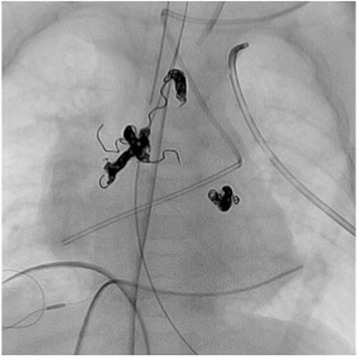

Fig. 2.

Three abnormal collateral arteries are embolized with 12 Orbit Galaxy detachable coils